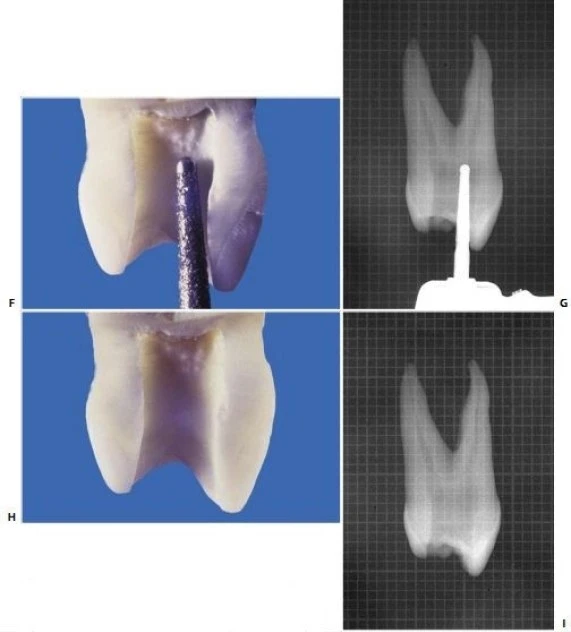

Dùng mũi khoan đầu trơn với tay khoan siêu tốc tạo hình dáng của xoang mở tủy ở giai đoạn hoàn thành và làm loe (hình 11.44 F,G). Hình dạng của xoang mở tủy khi hoàn thành có hình trứng với đường kính lớn hơn theo chiều ngoài trong và nó thường không liên quan đến đỉnh múi (hình 11.44 H, I). Việc nó có liên quan đến đỉnh múi hay không tùy thuộc vào góc phân kỳ giữa hai chân răng và của hai ống tủy: nếu càng phân kỳ thì xoang tủy càng nhỏ, nếu càng song song thì xoang tủy càng có khả năng phạm đến múi răng. Hai ống tủy thường giao nhau tại một rãnh cạn, ta có thể xác định được rãnh này nếu kiểm tra kỹ sàn buồng tủy (hình 11.45).

. Hình 11.44. (tiếp theo) F. Dùng mũi khoan kim cương ở giai đoạn hoàn thành và làm loe. G. Hình ảnh X-quang của giai đoạn hoàn thành và làm loe. H. Xoang tủy đã hoàn thành. I. Hình ảnh X-quang: múi vẫn còn nguyên.